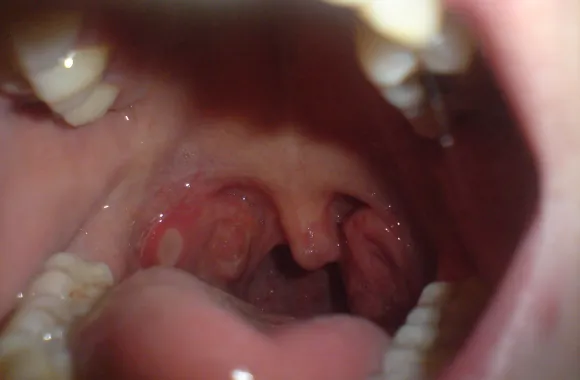

- Ropny nalot na migdałkach lub białe plamy w gardle.